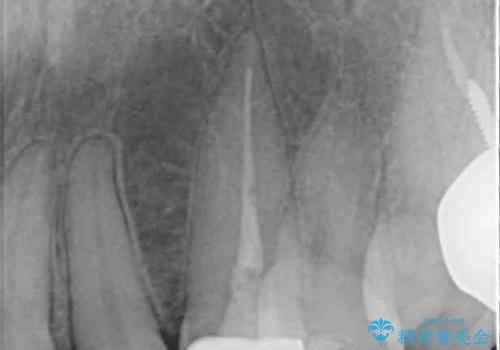

土台の金属を除去してファイバーコアによる土台植立を行い、オールセラミッククラウンにて補綴することとしました。

保険診療では樹脂を用いた素材で製作するため、水分が吸収されやすく、一緒に色素が取り込まれるために変色をしてしまいます。

また、裏打ちに主に銀を用いた金属材料を使用するため、金属自体が黒くなったり、イオンとなり溶け出したりして、歯肉ラインが黒くなってしまうことがあります。